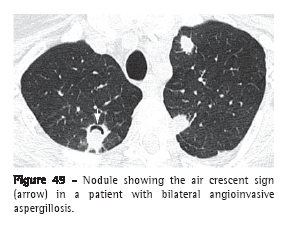

Air crescent sign (sinal do crescente aéreo)

The air crescent sign corresponds to a collection of air of variable size and in the form of a crescent or half moon, located in the periphery of a nodule or mass and presenting soft tissue density; in the proper clinical context, this finding is suggestive of angioinvasive aspergillosis in the recovery phase (Figure 49).(77-79) In this case, the air crescent sign is secondary to the retraction of infarcted pulmonary parenchyma and the resorption of necrotic tissue in the peripheral region of the lesion, causing the space between the dead tissue and the adjacent parenchyma to be filled by air.(78) This sign is also used to describe the findings of the fungus ball, in which there is a collection of air surrounding the intracavitary lesion or interposed between the upper wall of the preexisting cavity and the hanging intracavitary lesion (Figure 7).(7) The air crescent sign has also been described in other diseases, such as intracavitary hemorrhage, bacterial abscess and lung cancer.(80,81)